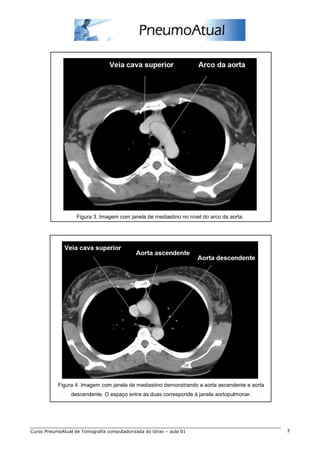

Figura 3. Imagem com janela de mediastino no nível do arco da aorta.

Figura 4. Imagem com janela de mediastino demonstrando a aorta ascendente e aorta

descendente. O espaço entre as duas corresponde à janela aortopulmonar.

Figura 3. Imagemcom janela de mediastino no nível do arco da aorta. Figura 4. Imagem com janela de mediastino demonstrando a aorta ascendente e aorta descendente. O espaço entre as duas corresponde à janela aortopulmonar. Curso PneumoAtual de Tomografia computadorizada do tórax – aula 01 3